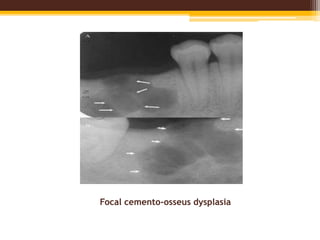

Focal Cemento-Osseus Dysplasia

• Exhibits a single site of involvement.

• Most commonly in black females with a

predilection for 3-6 decade.

• Posterior mandible is the commonest site.

• Usually asymptomatic with a positive vitality

test of the affected teeth.

• Most of the lesions are smaller than 1.5cm in

diameter.

Radiographic Features

• Lesions vary from being completely radiolucent to

densely radiopaque with a thin peripheral

radiolucent rim.

• Most common is a mixed radiolucent and

radiopaque pattern.

• Well defined lesion with a slightly irregular border.

• Occurs in both dentulous and edentulous areas.